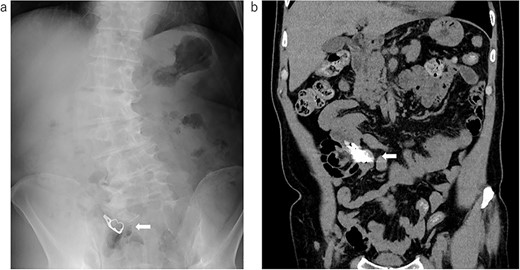

Under general anesthesia, the abdomen was opened with a small incision of 5 cm in the mid-abdomen. There were no ascites or adhesions. The foreign body was palpated in the jejunum, 60 cm from the ligament of Treitz. There were no abnormal findings on the serosal surface (Fig. 3a). An incision was made in the small intestine, and the foreign body was tried to remove. However, the hook part was tightly involved with the mucosal membrane and could not be removed (Fig. 3b). Therefore, when we tried to bend the hook portion with forceps, the hook portion was damaged, and as a result, extraction became possible (Fig. 3c). After confirming that there was no damage to be repaired on the mucosal surface and that no foreign matter had fallen into the abdominal cavity, the incised small intestine was closed with sutures.

Intraoperative photograph and image of the removed denture; (a) the small intestine removed outside the body: there were no abnormal findings on the serosal surface; (b) a denture found in the small intestine: the hook part involved the small intestinal mucosa; (c) removed denture: the hook part is damaged during extraction.